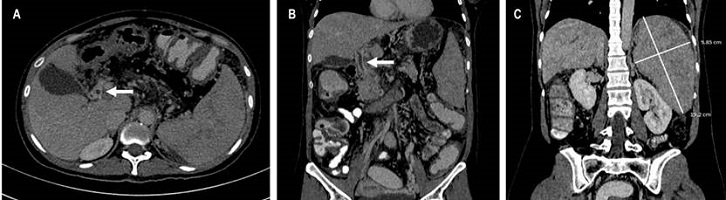

Se practicó la aspiración del contenido y no se consideró alguna conducta quirúrgica adicional; posteriormente, se decidió realizar una angiografía abdominal en la que se encontró una trombosis de la vena esplénica, mesentérica y vena porta intrahepática con circulación colateral y cortocircuito fisiológico esplenorrenal asociada con esplenomegalia y permeabilización de la vena gástrica izquierda (Figura 1). Se indicó anticoagulación con heparina de bajo peso molecular (HBPM) y bloqueante β no selectivo.

Dado que las principales causas de trombosis en estos sitios son las trombofilias, se realizaron estudios pertinentes (Tabla 1) en los cuales solo se identificó una mutación de la JAK2V617F y el hemograma mostró hallazgos relacionados con anemia leve; debido a lo anterior, se solicitaron niveles de eritropoyetina (EPO), que se encontraron dentro de los parámetros normales, por lo cual se consideró una NMP en forma latente.

Además, se realizó una agregometría plaquetaria, la cual evidenció hiperagregación a dos concentraciones tanto con ADP como epinefrina (Figura 2) y se clasificó como síndrome de plaqueta pegajosa (SPP) tipo 1. Una vez presentó mejoría clínica, se indicó la anticoagulación en modalidad off-label o no aprobado con rivaroxabán 20 mg/día.